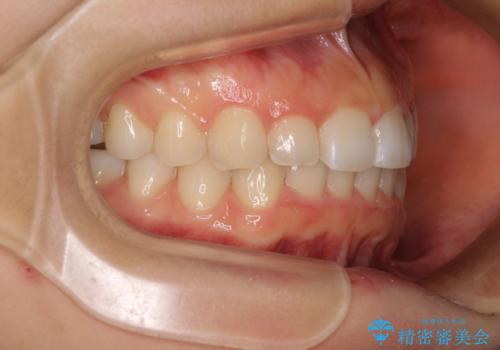

前歯のデコボコと突出感 インビザラインによる矯正治療

- 上下前歯のデコボコと、上顎前歯の突出感を気にして来院された患者様です。

インビザラインによる上下歯列の側方拡大と後方移動、IPR(歯と歯の間を削る)にるスペースの獲得により歯列を整えることとしました。

毎日22時間以上しっかりとマウスピースを装着していただいたので、スムーズに治療が進みました。歯と歯の間を削ることでうまくスペースコントロールでき、1年強で終えることができました。